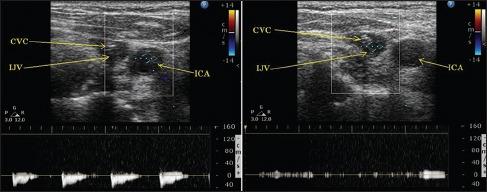

Arterialization of central venous pressure waveform.